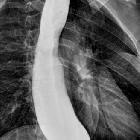

Fluoroscopy with barium swallow

A barium swallow study may be used to confirm esophageal dilatation, in addition to assessing for mucosal abnormalities.

Findings include:

- bird beak sign or rat tail sign

- esophageal dilatation

- tram track appearance: central longitudinal lucency bounded by barium on both sides

- incomplete lower esophageal sphincter relaxation that is not coordinated with esophageal contraction

- pooling or stasis of barium in the esophagus when the esophagus has become atonic or non-contractile (a late feature in the disease)

- uncoordinated, non-propulsive, tertiary contractions (see case 1)

- failure of normal peristalsis to clear the esophagus of barium when the patient is in the recumbent position, with no primary waves identified

- when the barium column is high enough (with the patient standing), the hydrostatic pressure can overcome the lower esophageal sphincter pressure, allowing passage of esophageal content